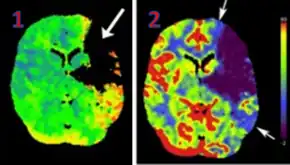

CT perfusion with flow and volume maps in cerebral infarction

Perfusion CT or CT Perfusion is a type of Perfusion Scanning using Computed Tomography. It is helpful in evaluation of the vascularity of a tissue in the body. In this the temporal changes in the tissue density are measured which gives the information about the vascularity of the tissue. In CT perfusion injection of contrast media is given and then the scan is taken. The acquired data are then post-processed to obtain perfusion maps with different parameters, such as BV (blood volume), BF (blood flow), MTT (mean transit time) and TTP (time to peak).[1][2]

CT Perfusion plays an important role in the assessment of Acute Ischemia Stroke. It is used to create maps of blood flow, blood volume and mean transit time to assess the tissue and to differentiate between core and penumbra in stroke.[3]